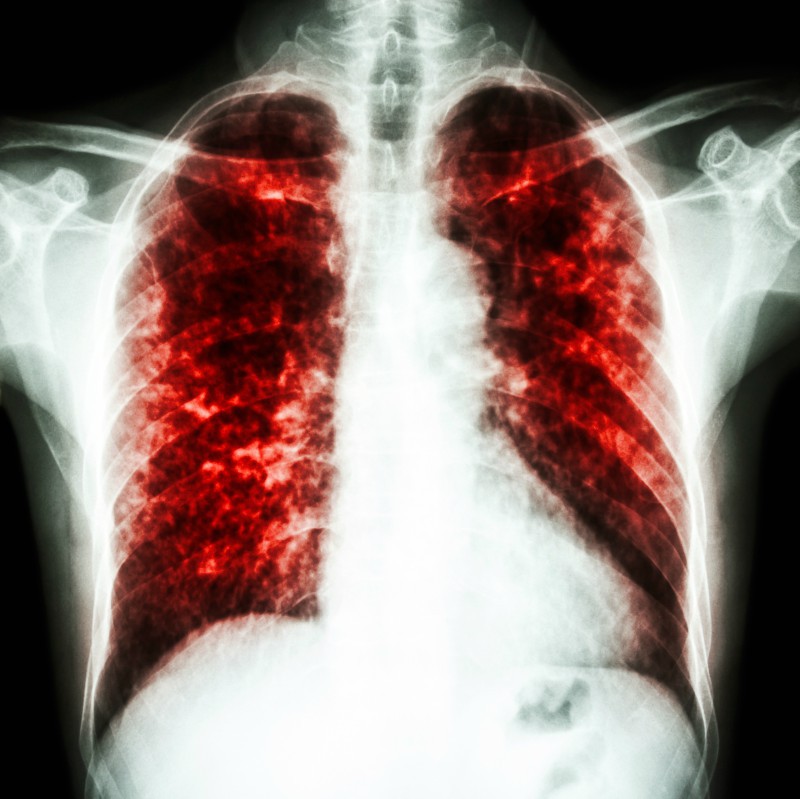

Pneumonia este o infectie acuta a plamanilor care poate fi determinata de un numar mare de microbi virusuri sau bacterii si care se vindeca in majoritatea cazurilor in conditiile unui diagnostic precoce si a unui tratament corect.

Are scopul de a identifica cauze rare ale pneumoniei ex tumori bronsice benigne maligne carcinoid sau corp strain inhalat in bronhii si de a recolta secretii. Carol dersarkissian spune ca este nevoie de minim 3 saptamani pana va refaceti de la pneumonie. Pneumonia este o infectie a unuia sau a celor doi plamani cauzata de obicei de virusuri bacterii sau fungi. Inainte de descoperirea antibioticelor o treime din oamenii care sufereau de pneumonie au decedat din cauza infectiei.